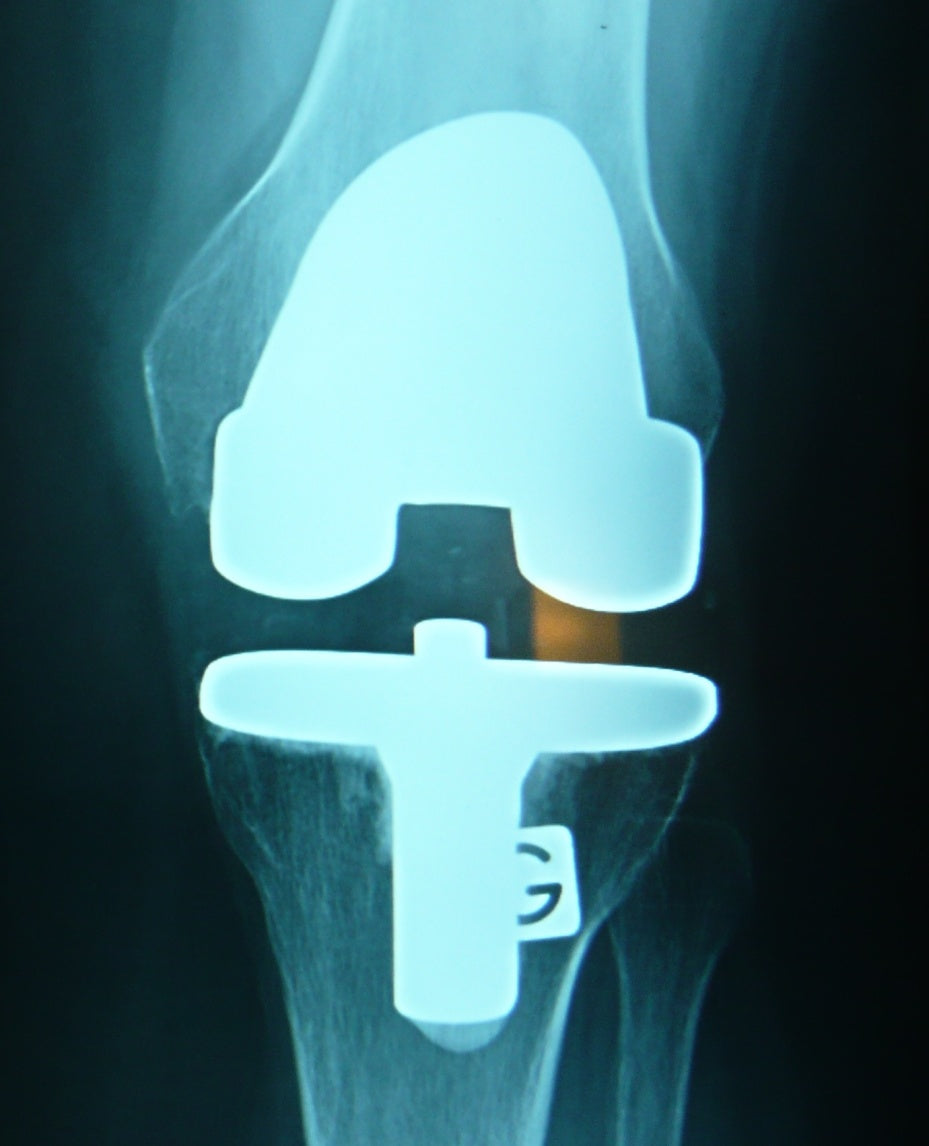

La destruction progressive du cartilage observée pendant l’arthrose est due à une inflammation chronique des chondrocytes. Pourquoi les chondrocytes s’enflamment-ils ? Le plus souvent parce qu’ils ont subi un traumatisme. Cela peut être le cas des articulations du doigt et du poignet chez les personnes qui travaillent sur clavier d’ordinateur, celles de la main ou du coude chez les musiciens, celles du genou et de la colonne vertébrale chez les footballeurs et les rugbymen. Les personnes qui pratiquent des métiers manuels comme les maçons, les peintres, les agriculteurs souffrent plus fréquemment d’arthrose de l’épaule.

Le surpoids est également à l’origine de l’inflammation des chondrocytes, en particulier au niveau des genoux ou de la hanche, à cause de la pression qui s’exerce sur l’articulation.